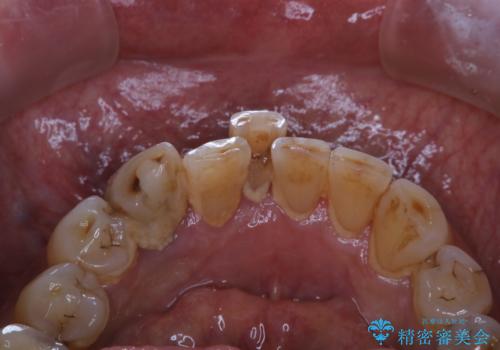

半年ぶりのクリーニング PMTC

- 半年、来院できなかったためきれいにクリーニングしたいとのことでした。久しぶりだったことと、全体的に汚れが付着していたためPMTC60分コースを行いました。

PMTCを行うとステインやバイオフィルム(細菌のかたまり)が除去され、ご自身本来の歯の状態になります。そのためスッキリとした爽快感が得られ、気持ちがいいです。また、口臭予防にもなります。